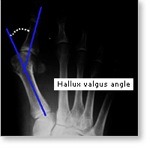

A Bunion is a common problem that most people experience as a bony protuberance at the base of the big toe. The problem, however, is more complicated than simply a bump. Bunions are most commonly due to the big toe angling in towards the other toes, a condition called hallux valgus.

X-rays will be taken to determine the extent of displacement of the bones making up the bunion. The angles shown here help us decide which bunion operation would be the best. This is the angle between the 1st and 2nd metatarsal.